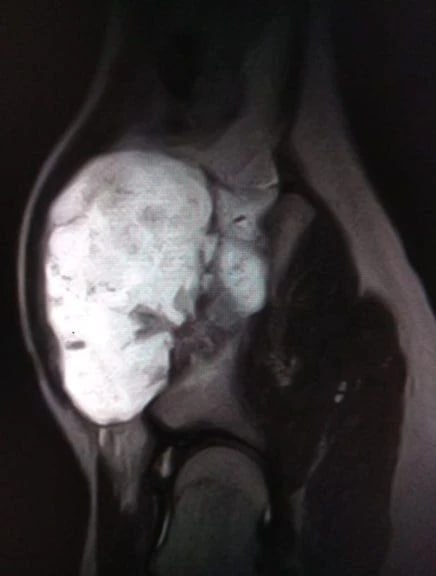

13-летний парень наблюдался в больнице с редким диагнозом – экзостозная хондродисплазия. При таком заболевании кости образуется костно-хрящевое разрастание. У пациента появилось образование 12 на 9 на 7 см на подвздошной кости. Нарост болел и причинял дискомфорт, кроме того, образование угрожало здоровью тазобедренного сустава.